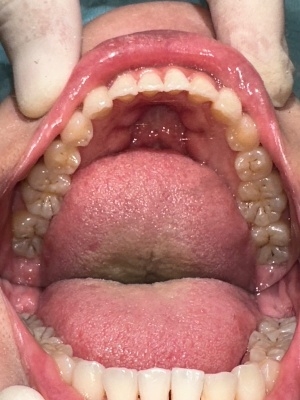

下顎